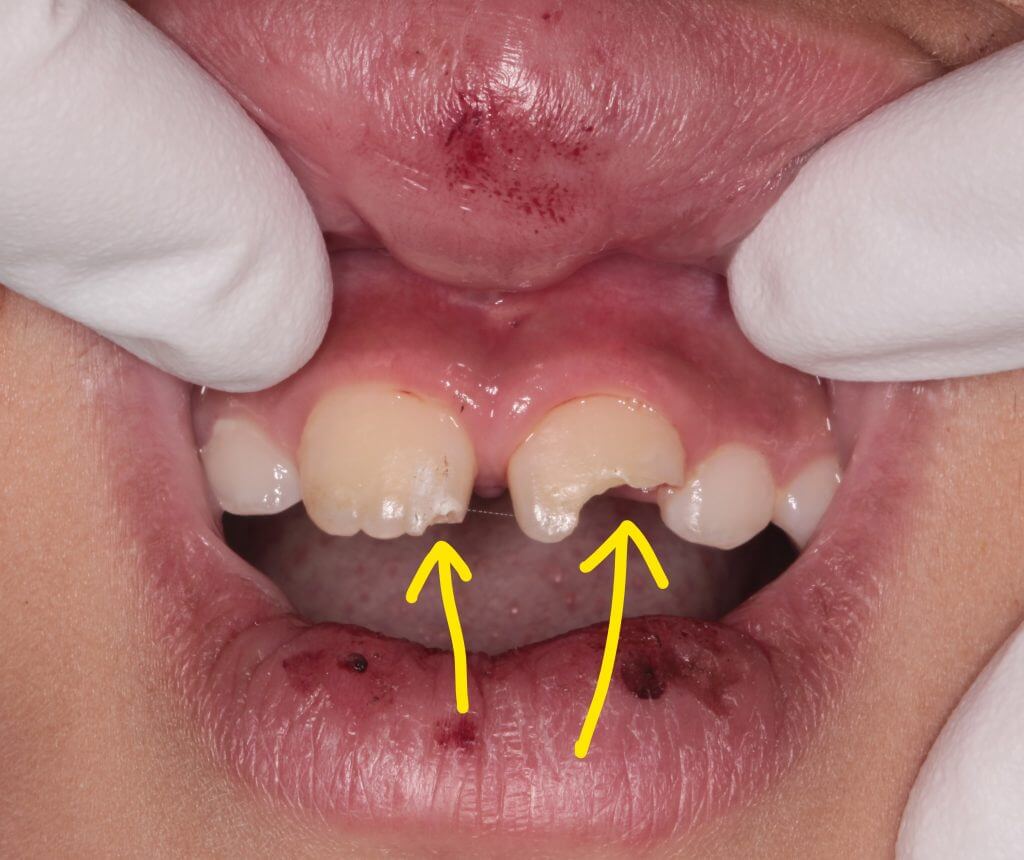

朝、子供が学校への登校中に前歯を強打したということで来院

お母さんが心配されて来院されました。

歯牙の破折は右側と左側に認められます。

口腔内所見では露髄は認められず臨床症状もないため神経には問題はなさそうでした。レントゲン所見でも問題なかったので修復処置に移ります。今回は左側の大きく欠けた歯の一部をお母さんが探して持ってきていたので、それをコンポジットレジンで接着して修復の一部に再利用することとしました。